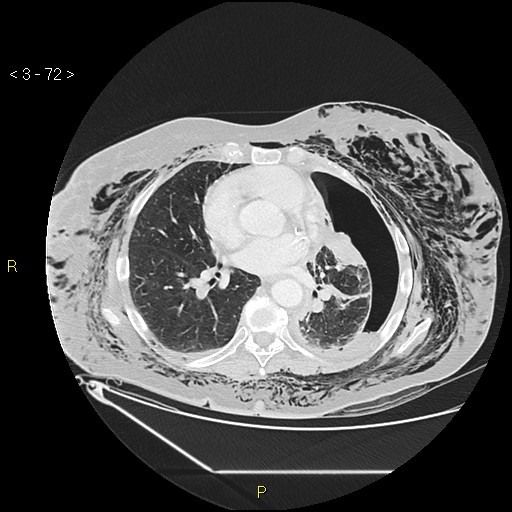

Imaging interpretation is a vital skill required for all those dealing with the multiply injured patient, not just the radiologist.

Management in trauma follows the ABCDE approach and radiological interpretation is no different. Consultant Radiologist Dr Nick Carter guides us through interpretation of the CT pan-scan as the radiology primary survey in trauma.

Images courtesy of Dr Derek Smith, Radiopaedia.org from the case rID: 36667, Dr Sajoscha Sorrentino, Radiopaedia.org from the case rID: 16291 and Dr Maxime St-Amant, Radiopaedia.org from the case rID: 20112